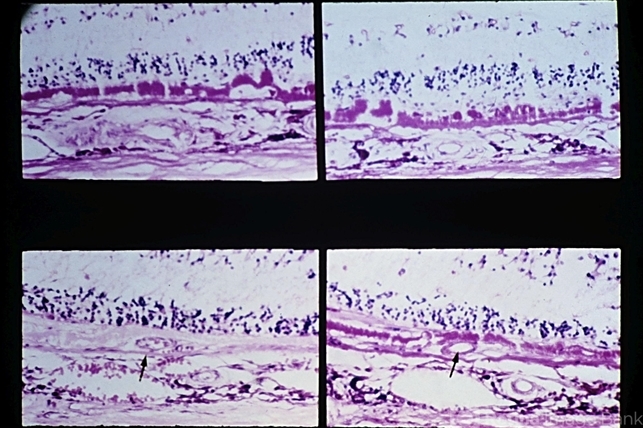

- macular degeneration, drusen, Bruch's membrane, retinal pigment epithelium, choroidal neovascularization (CNV)

- Senile macular degeneration. Note presence of drusen and diffuse thickening of the inner aspect of Bruch's membrane, areolar RPE and photoreceptor atrophy, and choroidal neovascularization (arrows).